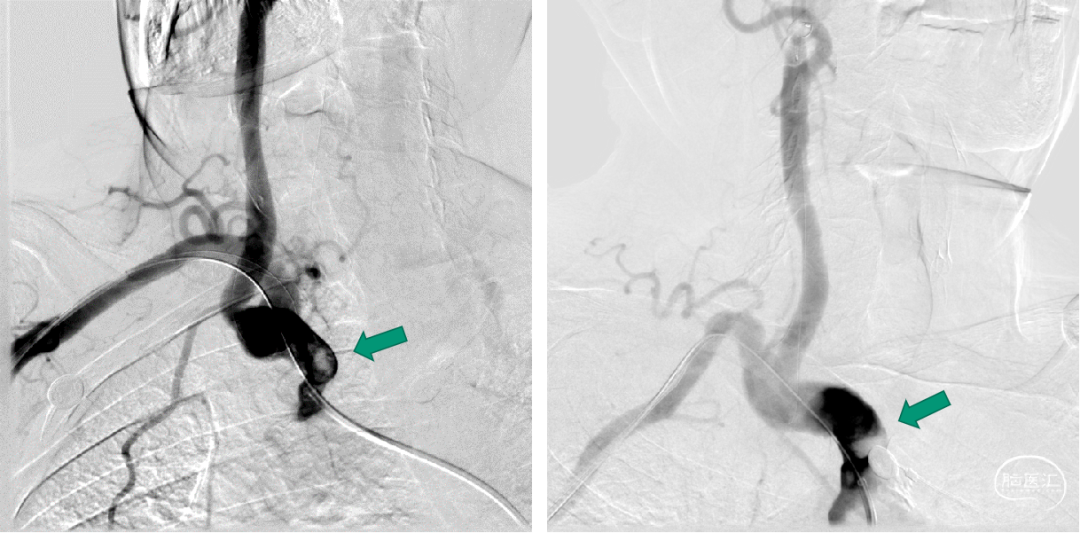

猪尾配合PILOT150外周导丝选入右侧颈总动脉内,交换6F Guiding方便路图指引操作。

引入5mm-320cm泰杰伟业颈动脉保护伞后,靠保护伞支导丝撑力将Guiding带入右侧颈总动脉,路图发现伞位置较低,颈内动脉C1段严重迂曲,上调保护伞位置至颈内动脉C1段弯下平直处。

右侧椎动脉内置入5mm-190cm泰杰伟业保护伞。

125cm MPA配合泥鳅导丝选入右侧锁骨下动脉内,同轴技术跟进NeuronMAX至头臂干起始处造影可见血栓影。

头臂干直径13mm,无相应的球扩式支架,且球扩过程中容易挤碎血栓,因此考虑自封式支架更合适。

编制支架近端定位困难,编制支架自膨后长度难以把控。因此选用支架选用开环,网孔相对较密的9×30 Precise颈动脉支架。

冒烟下根据血栓位置定位支架位置。

支架半释放后再次冒烟确认支架完全覆盖血栓,且弓下不会露出太长后释放支架。

支架释放后造影可见支架完全覆盖血栓,位置良好,椎动脉血流缓慢,可能有血栓脱落。

半回收保护伞依次回收颈动脉保护伞和椎动脉保护伞。

颈内动脉和椎动脉保护伞都发现血栓。

取出保护伞后椎动脉流速恢复正常,颅内未发现明显的大血管栓塞。